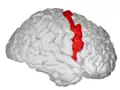

| Precentral gyrus | |

![]() Precentral gyrus a prominent gyrus of the frontal lobe | |

The precentral gyrus is a prominent gyrus on the surface of the posterior frontal lobe of the brain. It is the site of the primary motor cortex that in humans is cytoarchitecturally defined as Brodmann area 4.

The precentral gyrus lies in front of the postcentral gyrus - mostly on the lateral (convex) side of each cerebral hemisphere - from which it is separated by the central sulcus. Its anterior border is represented by the precentral sulcus, while inferiorly it borders to the lateral sulcus (Sylvian fissure). Medially, it is contiguous with the paracentral lobule.